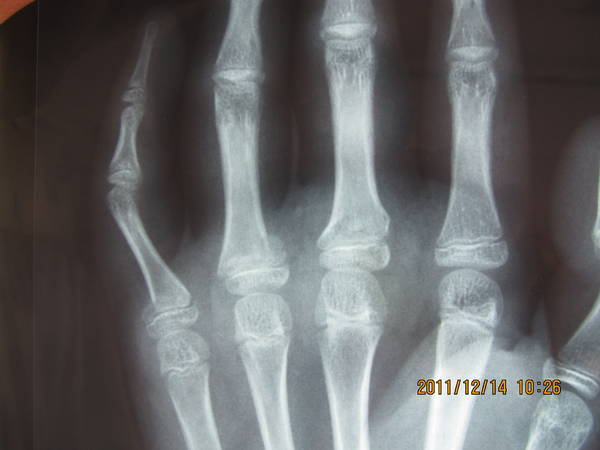

[修复重建] 小儿手指骨骺损伤如何处理

小儿 骨骺损伤

患儿,男性,13岁。

个人认为小指近节基底骨折成角旋转角度需要干预,至于如何干预,请大家讨论。

小指已明显旋转畸形,切开复位克氏针固定应该好一点,一月即可拔出克氏针